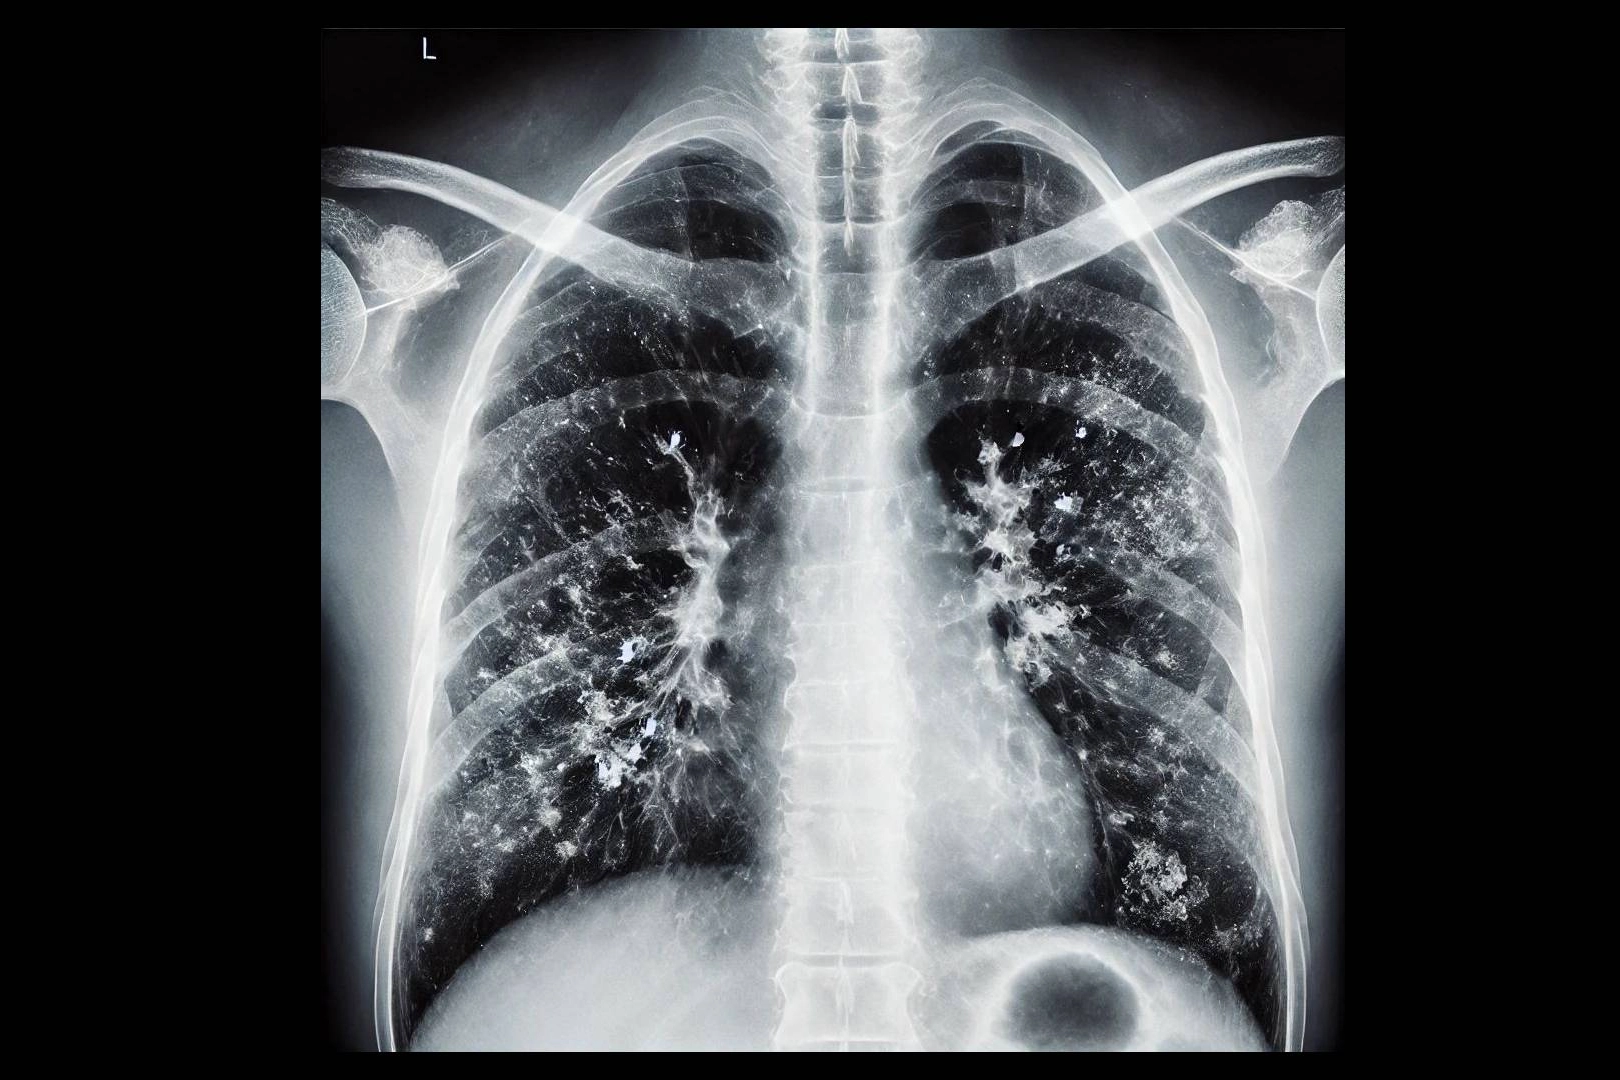

Mevsimsel grip, nezle ve diğer solunum yolu enfeksiyonları genellikle hafif seyretse de bazı durumlarda zatürreye dönüşerek ciddi komplikasyonlara yol açabiliyor. Uzmanlar, zatürrenin grip ya da soğuk algınlığıyla karıştırılabileceğini fakat bazı kritik belirtilerin ayırt edici olduğunu söylüyor. Yüksek ateş, titreme, aşırı halsizlik, balgamlı ve koyu renkli öksürük, nefes darlığı ve göğüs ağrısı gibi şikayetlerin zatürre ihtimalini güçlendirdiğini belirten uzmanlar, zatürrenin özellikle yaşlılar, bebekler ve kronik hastalığı olan bireylerde ağır seyredebileceğini belirtiyor.

Zatürrenin grip ya da soğuk algınlığıyla karıştırılabileceğini belirten Prof. Dr. Özlü, "Bu tür enfeksiyonlar genelde üst solunum yollarında yerleşir. Oradan başlar ve nezle, soğuk algınlığı, farenjit, sinüzit gibi üst solunum yolu enfeksiyonlarına yol açar. Bazen de alt solunum yollarına ilerleyerek bronşit, bronşiolit gibi hafif hastalıklara yol açabilir. Fakat zatürre, bu hastalıklar arasında en ağır olanıdır. Maalesef, şu sıralar pek çok hasta zatürreyi fark edemiyor ve teşhiste geç kalıyor. Oysa zatürrede erken tanı çok önemli. Hekimin, 4 saat içinde doğru tedaviye başlaması, zatürreye bağlı ölümleri anlamlı şekilde azaltıyor" ifadelerini kullandı.

Zatürre ve soğuk algınlığı arasındaki farklara dikkat çeken Özlü, "Şöyle ki; 'Zatürre mi, soğuk algınlığı mı?', 'Zatürre mi, yoksa bronşit gibi bir alt solunum yolu enfeksiyonu mu?', bu ayrımın yapılması lazım. Bu ayrımı bir göğüs hastalıkları uzmanı yapabilir. Ancak hastalar, 'Ben zatürre olup olmadığımı nasıl anlarım?' diye soruyor. Aslında tüm solunum yolu enfeksiyonlarında; ateş, halsizlik, kırgınlık, boğaz ağrısı, öksürük, burun akıntısı, geniz akıntısı, burun tıkanıklığı gibi semptomlar olabilir. Ancak zatürrede bu şikayetlerin çok daha ağır seyrettiğini biliyoruz. Ateşiniz çok yüksekse, üşüme ve sıtma nöbetleri oluyorsa, aşırı bir takatsizlik ve bitkinlik durumu varsa, genel sağlığınızı bozuyor, yeme ve içmenizi aksatıyorsa zatürre olma olasılığı yüksektir" diye konuştu.

Zatürre tanısında en önemli belirtilerin nefes darlığı ve öksürük olduğunu ifade eden Özlü, "Şikayetleriniz tedaviyle ya da tedavisiz olarak ilk birkaç gün içinde azaldıktan sonra tekrar ikinci bir atak yaşanıyorsa; ateşlenme ve şikayetlerde artış oluyorsa bu da zatürrenin eklendiğini gösterebilir. Nefes darlığı çok önemli bir belirti. Özellikle nefes alıp vermekte zorlanıyorsanız, özellikle bebeklerde ve yaşlılarda solunum sayısının dakikada 24'ün üzerine çıkması, nefes alıp verirken hırıltı olması, bebeklerde burun kanatlarının solunuma eşlik etmesi, nabız sayısının dakikada 120'nin üzerine çıkması gibi durumlar zatürre olasılığını güçlendirir. Öksürük de önemli bir belirti. Zatürrede öksürük genellikle yaş öksürüktür. Yani balgamlıdır. Balgamın koyu renkli olması; kahverengi, koyu sarı, koyu yeşil gibi ve kıvamlı olması zatürre ihtimalini artırır. Ateşin çok yüksek olmasıyla birlikte yan ağrısı dediğimiz, öksürürken ya da nefes alırken batıcı şekilde hissedilen bir yan ağrısı varsa, bu da zatürreye işaret edebilir" dedi.